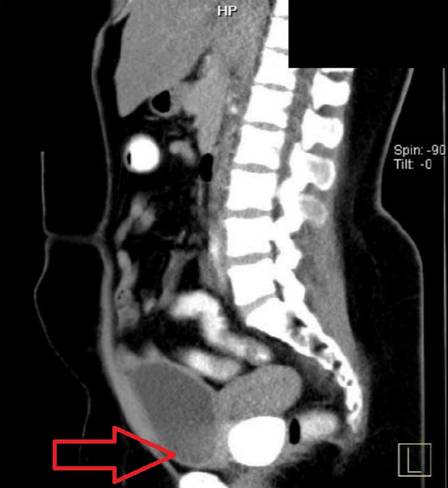

Um exame simples, porém, levantou sinais de que algo estava obstruindo a vagina. Exames de imagem a seguir mostraram duas pedras “sólidas e lisas” dentro da área pélvica.

Veja a imagem:

Exame detecta pedras vaginais em paciente na Indonésia – Foto: Reprodução/Urology Case Reports/NDExame detecta pedras vaginais em paciente na Indonésia – Foto: Reprodução/Urology Case Reports/ND